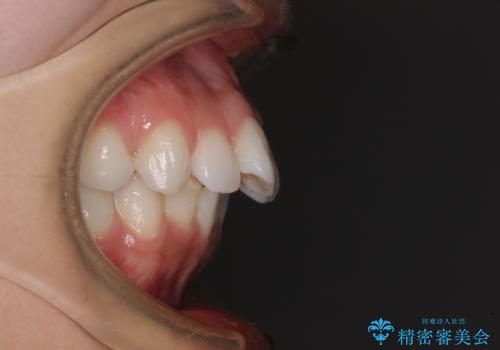

左右ともに奥歯の咬み合わせに問題があり、上顎臼歯が前方位にある状態で、結果として上顎前歯全体が前方位かつ叢生になっていました。

補助装置を用いて上顎歯列全体を後方に移動させ、下顎は左右で抜歯する小臼歯を変えることで、左右の咬み合わせをより理想的な位置となるように計画しました。